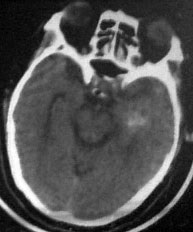

病人男性52岁,一年前曾患脑出血.今突发剧烈头痛,恶心,呕吐..病人家属说病人自去年脑出血以后,精神异常!请大家看看左侧颞叶病灶考虑什么?片子不是很清楚请大家见谅!!左颞叶病灶ct值最高处为85hu

左颞叶病灶我认为不是出血,就算是出血,也与右侧病灶性质不同。理由:1.该病灶密度较淡而不均匀,其间见斑点状更高密度。急性出血,应该不会是这个样子。

2.病灶对周围无推移挤压迹象,也无水肿。倒是病灶旁边、左侧环池局部扩张,与右侧病灶

完全不一样。

综合上诉特点,左颞叶病灶我首先考虑:avm。

左颞叶病灶我认为不是出血,因为边界不清,无水肿带,应该是散在钙化灶,不排除avm,建议增强.

左侧颞叶病灶密度不均,似见点状钙化,支持血管畸形性病变.右侧病变为出血.